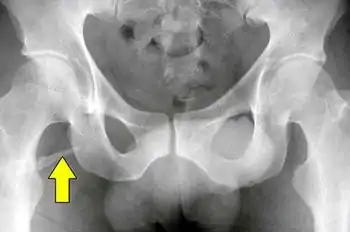

A pelvic digit, pelvic finger, or pelvic rib is a rare congenital abnormality in humans, in which bone tissue develops in the soft tissue near the pelvis, resembling a rib or finger and often divided into one or more segments with pseudo-articulations. Pelvic digits are typically benign and asymptomatic, and are usually discovered accidentally. Approximately 41 cases have been reported.[1]

The pelvic digit was first reported by D. Sullivan and W.S. Cornwell in 1974.[2] Pelvic digits may be located at any level of the pelvis, the lower ribs, or even the anterior abdominal wall. It is theorized that pelvic digit anomalies arise during the mesenchymal stage of bone growth, within the first six weeks of embryogenesis. Their formation may result from a failure of the primordium of the coccyx to fuse to the vertebral column, leading to the independent development of a proto-rib structure.[1]